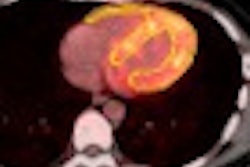

Meanwhile, "Advances in Cardiac Nuclear Imaging: SPECT/CT and PET/CT" is part of Wednesday's refresher course schedule. Presenters will help attendees understand the technical advancements associated with new scintillation cameras and SPECT/CT and PET/CT cameras. The discussion will include the benefits of CT attenuation correction, as well as the adjunctive benefits of anatomic definition provided with CT and physiologic and functional information provided by SPECT and PET (Wednesday, December 1, 8:30 a.m.-10:00 a.m., RC511, Room N230).